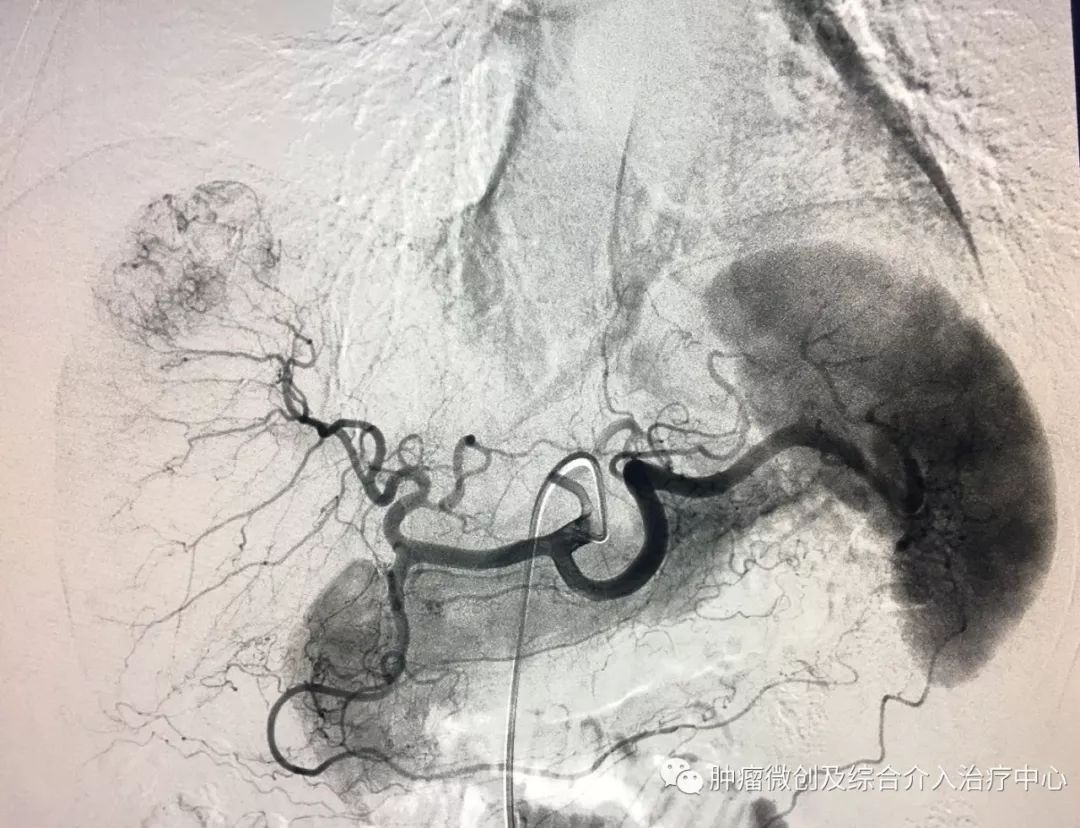

(鼻咽癌颈部转移瘤破溃出血,DSA造影提示左颈部病变血管迂曲、紊乱,内有出血)